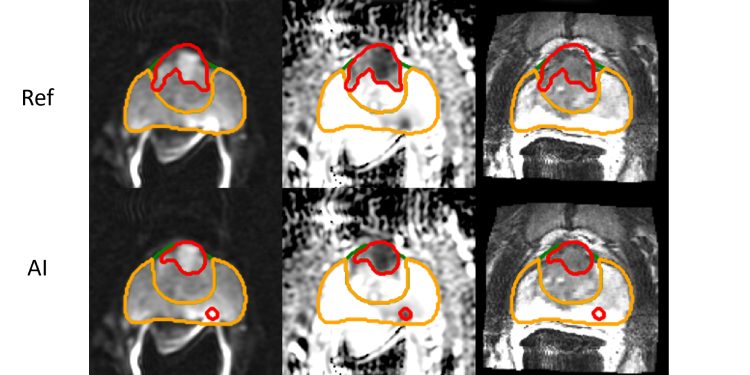

Prostat kanseri üzerine çalışan araştırmacılar, prostat kanseri tümörlerinin nasıl gelişebileceğini ve zamanla nasıl metastaz yapabileceğini hızlı bir şekilde tahmin eden yeni bir yapay zeka (AI) destekli model tanıttılar. Bu teknoloji, prostat MR’larını analiz etmek için bir segmantasyon algoritması kullanarak, kanserli tümörlerin detaylı konturlarını ortaya koymaktadır.

Çalışmayı gerçekleştirmek için araştırmacılar, NVIDIA GeForce RTX 3070 GPU ve PyTorch kullanarak görüntü analizi gerçekleştirdiler. Ayrıca, MRI verisetindeki görüntü segmentasyonu için nnUNet algoritmasını kullandılar. Model, 700’den fazla prostat kanseri hastasının MRI görüntüleri üzerinde eğitim ve test işlemi yaptı ve tümörlerin hacmini tahmin etme ile hastaların 5-10 yıl içindeki bilinen sonuçlarını karşılaştırdı.

Sonuçlar, modelin tümör hacmi ve konumunu tespit etmede insan uzmanıyla benzer doğrulukta, fakat çok daha hızlı olduğunu göstermiştir. Daha büyük tümörlerin hacim olarak metastaz veya nüks etme olasılığı ile daha yüksek ilişkiye sahip olduğu ortaya konmuştur. Araştırmacılar, henüz sınırlı sayıda MRI incelendiğine dikkat çekerek, sonuçların ümit verici olduğunu belirtmektedir.